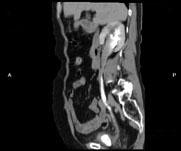

问题 女,64岁,反复尿频尿急尿痛6年余,尿常规检查:红细胞(++),白细胞(++)CT扫描如图示,下列说法正确的是 ( )

选项 A、考虑为慢性输尿管炎 B、考虑为输尿管移行细胞癌 C、右肾积水 D、右侧输尿管上段扩张 E、右侧输尿管下段管壁增厚,管腔狭窄

答案 ACDE